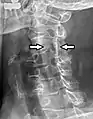

![]() Грудний хребець. Міжхребцеві отвори позначені стрілками | |

Проекційна рентгенограма чоловіка з болем у потилиці та лівому плечі зі стенозом лівого міжхребцевого отвору шийного відділу 4-го спинномозкового нерва через вікові дегенеративні зміни, що відповідають ураженому дерматому.